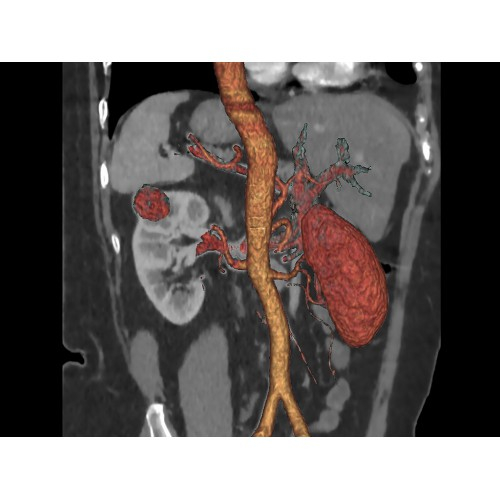

• Широкая область применения: от неврологии до кардиологии и онкологии.

КТ аппарат GE Optima CT520 используется для диагностики широкого спектра заболеваний:

Онкология

• Раннее выявление новообразований и контроль эффективности лечения.

• Планирование лучевой терапии с высокой точностью.